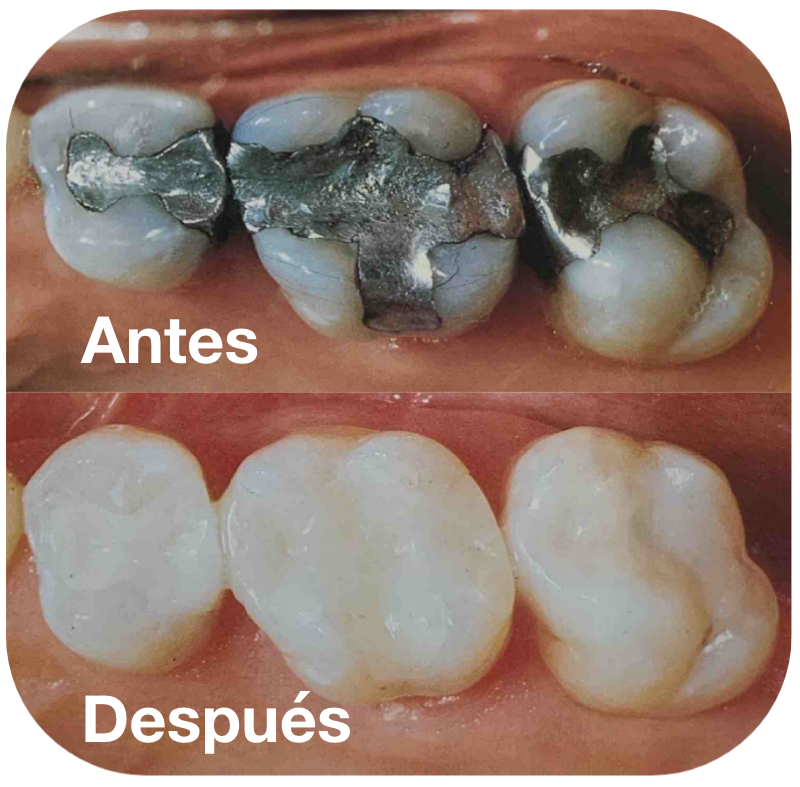

Es por eso que ofrecemos el servicio de restauraciones cerámicas, una solución moderna y estética para restaurar dientes dañados por caries, fracturas o traumatismos.

Nuestro equipo de profesionales altamente capacitados, utiliza materiales de restauración del mismo color del diente para lograr resultados sorprendentes y una sonrisa impecable.

Las incrustaciones, carillas y restauraciones con Composite son materiales restaurativos versátiles y de alta calidad que se adaptan perfectamente al color y forma de tus dientes naturales.

Utilizamos materiales de restauración de la más alta calidad, para lograr igualar la anatomía natural del diente y de esta manera lograr una masticación funcional y una sonrisa impecable.